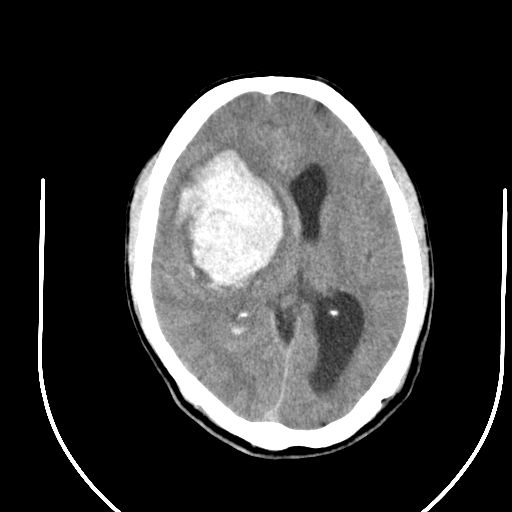

标题: CT24997:M,60Y,突发昏迷30分钟,有高血压病史。 [打印本页]

标题: CT24997:M,60Y,突发昏迷30分钟,有高血压病史。

右侧基底节区脑出血并破溃入脑室。

1右侧基底节脑出血伴脑干出血并破入脑室系统脑疝形成2梗阻性脑积水

1)右侧基底节脑出血伴脑干出血并破入脑室系统。2)大脑镰下疝。3)梗阻性脑积水。

1、右侧基底节脑出血伴脑干出血并破入脑室系统。

2、大脑镰下疝。

3、梗阻性脑积水。